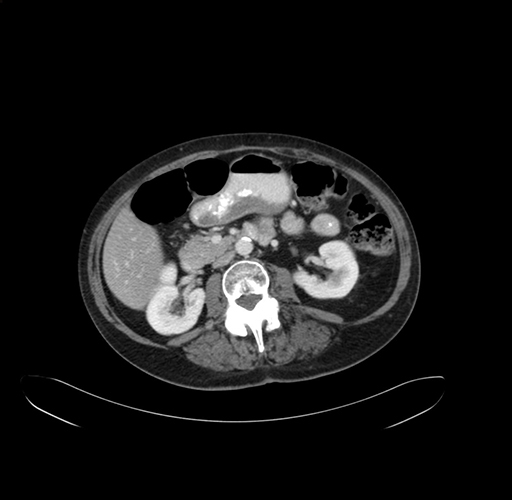

Pre-Chemo: Axial Venous